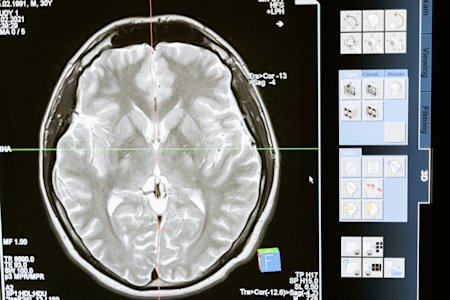

Naturally, radiologists can’t pack up MRI machines and bring them home. However, remote access technology can help radiologists access their work devices to view scans, securely access health records, and consult with other experts, no matter where they are.

Picture Archiving and Communication System (PACS) that stores, manages, and distributes medical images from anywhere, using the Digital Imaging and Communications in Medicine (DICOM) format to ensure they’re visible and accessible across devices.

AI-powered diagnostics to analyze medical images for patterns connected to diseases and injuries.